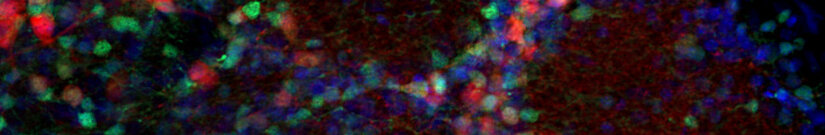

Dopaminergic Neurons

Dopaminergic neurons are collections of neurons in the central nervous system that synthesize the neurotransmitter dopamine. Loss of dopaminergic neurons is associated with neurological diseases, e.g. Parkinson’s disease and schizophrenia.